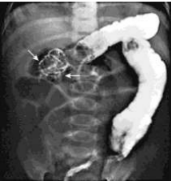

57.一歲男童,一夜尖叫不安,拒絕進食。在急診 X 光檢查結果如下圖所示,下列何者是最可能的診斷?(A) Intussusception(B) Celiac disease(C) Intestinal lymphoma(D) Hirschsprung’s disease